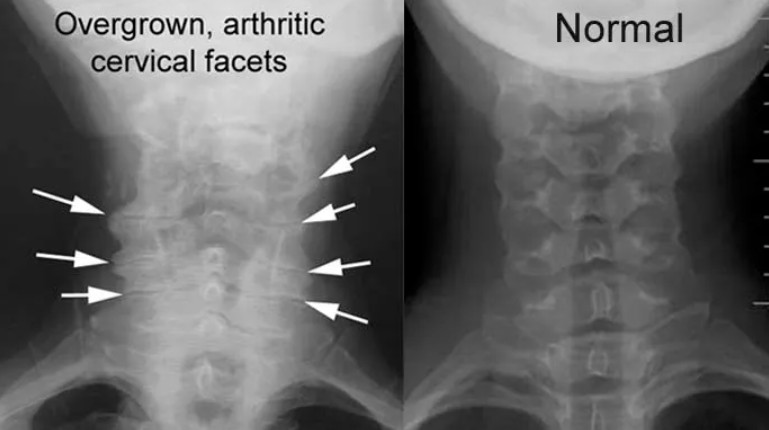

Cervical facet arthrosis

The facet joints in the back part of the cervical spine can also wear out in a similar manner.

In the images shown here, which are AP views (looking from front to back), arthritic and enlarged facet joints can be compared to more normal appearing joints.